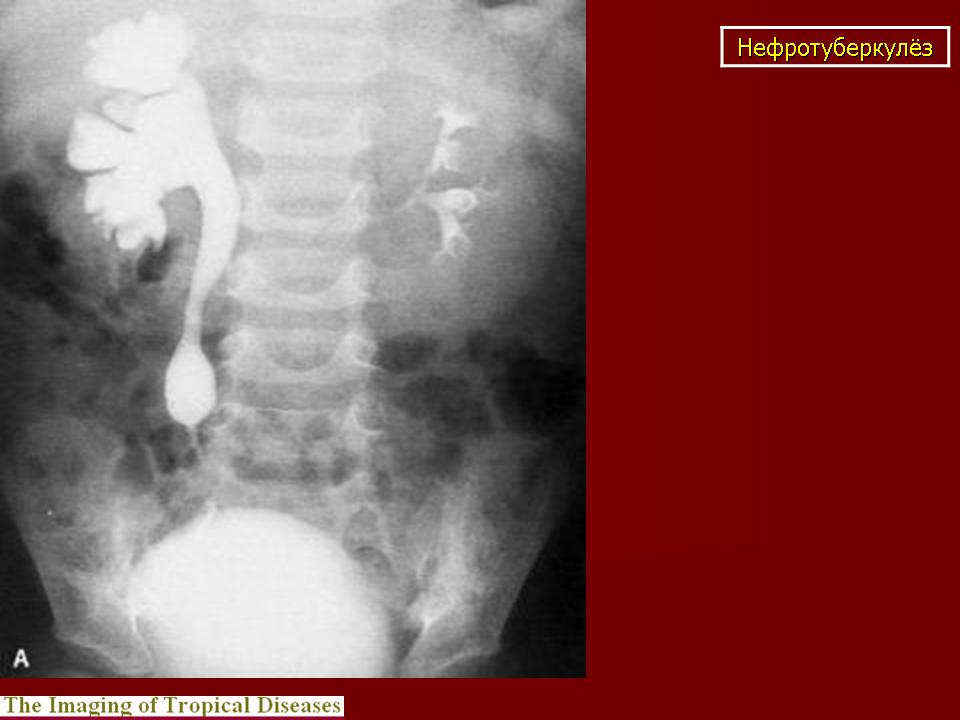

Рентгенологические методы исследования: флюорография (рентгенография) легких, обзорная и внутривенная урография в различных модификациях, томография почек, ретроградная пиелография, цистография, уретроцистопростатография, ангиография и др. Обзорный снимок мочевых путей позволяет обнаружить обызвествления в органах мочеполовой и других систем, изменения опорно-двигательного аппарата (туберкулезный спондилит, метастазы при раке почки и т. п.), определить контуры и размеры почек (увеличение или уменьшение, выбухания, втяжения). По внутривенной урограмме оцениваются функциональное состояние почек и анатомические особенности чашечно-лоханочной системы, мочеточников, мочевого пузыря; урография - основной рентгенологический метод исследования. Соответственно форме и стадии нефротуберкулеза могут быть выявлены; при субклиническом нефротуберкулезе - слабое контрастирование чашечно-лоханочной системы, хаотичное расположение чашечек, их деформация, при папиллите («начальном» деструктивном нефротуберкулезе) - неровность, стушеванность, нечеткость контуров чашечки ввиду наличия признака деструкции, при кавернозном туберкулезе - наличие полостей как в корковом, так и в мозговом слое с неровными, фестончатыми краями; при туберкулезном пионефрозе - изображение увеличенной почки с выбухающими неровными контурами, наличием больших полостей распада, нередко сливающихся между собой, резким снижением либо потерей функции (выключение - аутонефрэктомия); при нефросклерозе (вторично-сморщенная почка) - почка небольших размеров.

Начальный признак специфического поражения мочевых путей - расширение чашечно-лоханочной системы и мочеточника (снижение их сократительной способности в результате токсического воздействия, изменения функционального характера). Во всех случаях «неясной» уретерогидронефротической трансформации врач должен предположить наличие туберкулеза мочевой системы. В дальнейшем обнаруживают различные деформации чашечно-лоханочной системы (с уменьшением ее емкости) с явлениями гидрокаликоза; сужения мочеточника с расширением его выше стеноза; натянутость, четкообразную форму мочеточника; симптом подтянутости стенки мочевого пузыря; уменьшение емкости и различные деформации его контуров вплоть до появления двойного контура - симптома «песочных часов». При восходящей или микционной цистографии, урет-роцистопростатографии выявляют пузырно-мочеточниковый рефлюкс, а при последней - сужения уретры и затекание контрастного вещества в полости предстательной железы. Томографию почек применяют для уточнения контуров почки. Ретроградную пиелографию выполняют при неинформативности внутривенной урографии и для выяснения характера выключения туберкулезного очага (сопоставление пиело- и урографических данных). Ангиография позволяет получить представление об ангиоархитектонике пораженной почки, что важно при определении хирургической тактики.

Туберкулёз почки.